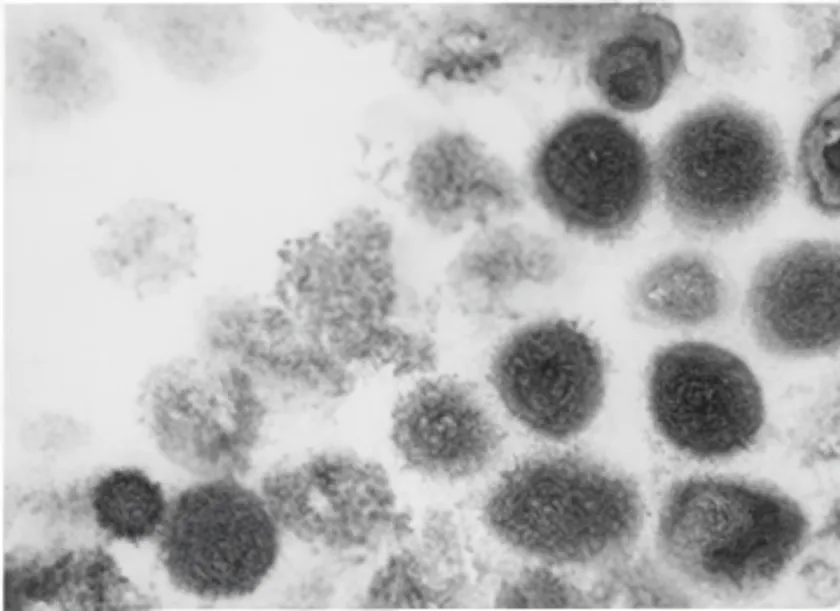

エムポックス顕微鏡写真

エムポックスは、モンキーポックスウイルスによる急性発疹性疾患で、感染症法では4類感染症に分類されます。発熱と発疹が主な症状で、多くは2~4週間で自然回復しますが、小児や免疫不全者では重症化のリスクがあります。